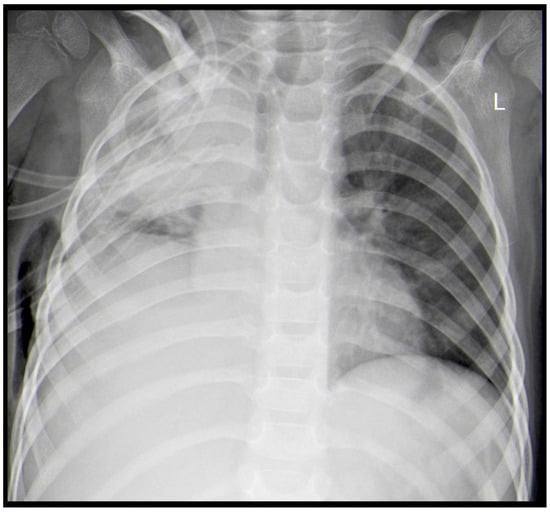

A Rare Case of Rhizomucor pusillus Infection in a 3-Year-Old Child with Acute Lymphoblastic Leukemia, Presenting with Lung and Brain Abscesses—Case Report

Invasive Mucormycosis (IM) is an extremely rare infection with a high mortality rate, caused by a group of fungi classified as Mucorales moulds. Rhizomucor pusillus is a saprophitic, thermophilic, and angioinvasive microorganism that grows and lives at about 45 °C and is usually found in different environmental spaces such as soil, air, water, food, and other organic matter. These features predispose the infection to wide dissemination, especially in immunocompromised patients and most often in children after chemotherapy for hematological malignancies (HMs). Mucormycosis in patients with hematologic malignancies and neutropenia represents between 0.07% and 4.29% of the concomitant diseases. IM can develop into an infection in different sites, but its most common manifestation is pulmonary, followed by rhino-orbital–cerebral and disseminated forms. In recent years, an increased morbidity rate has been associated with the ongoing COVID-19 pandemic, as cited in the literature. There are many publications with COVID-19-associated mucormycosis (CAM) cases. The present treatment protocol includes extensive and radical surgical debridement and systemic antifungal therapy with Liposomal Amphotericin B (L-AmB), Posaconazole, and Isavuconazole, either combined or as monotherapy. Despite these new treatment modalities, the mortality rate remains over 50%. We present a rare case of a 3-year-old child with acute lymphoblastic leukemia (ALL) and systemic Rhizomucor pusillus infection, diagnosed on the occasion of lung and brain abscesses. The patient underwent lung and brain surgery and is recovering well with no further complications. The two-year follow-up period shows no signs of recurrence of the disease. Full article

Show Figures

Figure 1